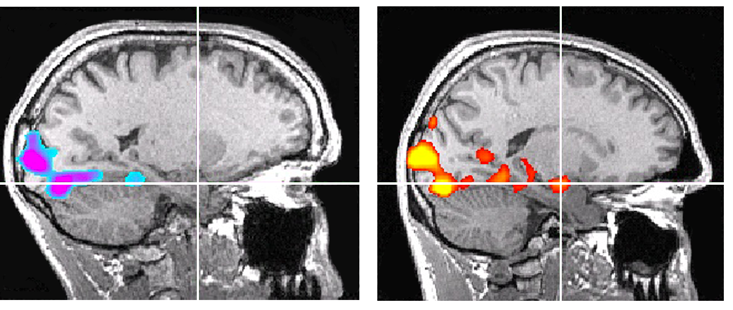

Tijdens dit onderzoek kwam ik een interessant artikel tegen in Nautilus (Het vreemde brein van ’s werelds beste soloklimmer). Een unieke inkijk kwam via een fMRI-scan uit 2016, waarin het brein van Alex Honnold werd vergeleken met dat van andere (top)klimmers.

De bevindingen sluiten opvallend goed aan bij wat we inmiddels weten over emotieregulatie en neuroplasticiteit.

Tijdens de scan kreeg Honnold circa 200 vreselijke beelden te zien die normaal gesproken sterke dreigingsreacties oproepen: geweld, verwondingen, brandende lichamen. Bij de meeste mensen en zelfs bij andere klimmers licht de amygdala dan direct op. Het alarmsysteem gaat aan (wat precies het doel van de beelden is).

De scan bevestigde dat Honnold beschikt over een amygdala. Maar toen die in de scan werd bekeken, was er bij Honnold vrijwel geen activiteit zichtbaar.

Zelfs toen de onderzoekers de meetlat lager legden, verscheen er maar één klein signaal in de amygdala, zo minimaal dat niet duidelijk was of het echte activiteit was of simpelweg ruis.

De conclusie was duidelijk: Nergens, op geen enkel betrouwbaar meetniveau, was er amygdala-activatie. Waar bij vrijwel iedereen het alarm afgaat, bleef het bij Honnold stil.

Honnold zelf noemde de angstbeelden “gedateerd” en “cynisch”. Alsof hij door een museum vol vreemde voorwerpen liep. Wat bij anderen paniek oproept, mist hier betekenis.

Dat roept een cruciale vraag op. Is zijn amygdala defect? Of is zijn regulatiesysteem uitzonderlijk krachtig?

De meest intrigerende hypothese sluit naadloos aan bij het eerdere emotieregulatiemodel: het kan zijn dat Honnold wél activatie voelt, maar dat zijn frontale cortex, betrokken bij planning, controle en remming, die activatie onmiddellijk dempt.

Met andere woorden: de angst komt op, maar krijgt geen podium.

Dan praat je dus niet over de afwezigheid van angst, maar juist meesterschap over angst.